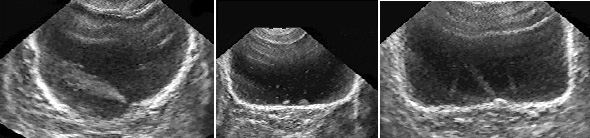

Рис. 16. Мочевой пузырь при цистите, лейкоцитурии. Определяется горизонтальный уровень нежной эхоструктуры (обозначен стрелкой), изменяющий свою форму и локализацию при перемене положения тела. (Поперечное сканирование, А − в положении пациента на спине, Б − на левом боку. Конвексный датчик 5 МГц, “Logiq-500”).

Рис. 17. Мочевой пузырь при цистите, пиурии. Вязкий гной образует причудливые фигуры на дне пузыря, при изменении положения тела он медленно перемещается, почти не меняя формы. (Поперечное сканирование, А − в положении пациента на спине, Б − на левом боку. Конвексный датчик 5 МГц, “Logiq-500”).